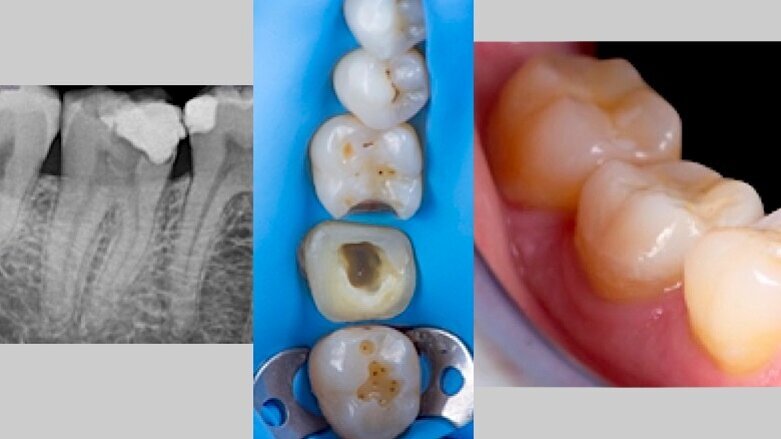

A continuación, y una vez acabado el tratamiento endodóntico y restaurador, procedemos con el tallado de la preparación de la restauración indirecta y el escaneado digital con el scanner Trios (3Shape). Se decide utilizar como material Celtra Duo (Dentsply) para la confección de un overlay para procurar un recubrimiento cuspídeo completo a este diente. Tras el fresado y confección de la incrustación, se efectúa un aislamiento absoluto con dique de goma, que va desde el 4.8 al 4.4 para su cementado (Figs. 6, 7, 8).

Fig. 9. Fotografía oclusal y lateral del resultado de la cementación de la incrustación indirecta en 4.7.

Fig. 10. Radiografía final del caso que muestra el tratamiento exitoso de conductos en el diente 4.7.